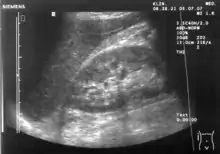

Ecografie abdominală

Aparatul funcționează pe principiul radarului. Sonda care se aplică pe corpul pacientului trimite ultrasunete către organul analizat, iar apoi receptează o parte din semnalul reflectat. Semnalul care se întoarce este analizat și transformat în imaginea vizibilă pe monitor în culorile albă și neagră.